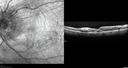

Grade 4 hypertensive retinopathy444 views55 year old man Hhe did have headaches a few weeks ago and also some nausea and vomiting. He noticed for a few weeks the vision in the left eye was blurred and that the vision in the left eye is dark.

VA OD: Dcc20/20

VA OS: Dcc20/100-1

He was admitted directly to ICU for blood pressure control (290 / 170 mmHg)

3 weeks later his VA increased to 20/20 OD, 20/32 OSJan 29, 2019